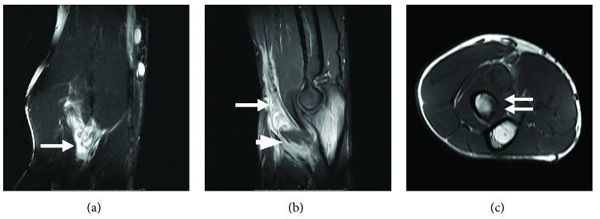

体格检查:右肘前窝肿胀,肱二头肌轻度压痛,试图旋转前臂和弯曲肘部时肌肉无力或疼痛。其他系统检查均正常。实验室检查显示白细胞计数高, 中性粒细胞计数为72%,淋巴细胞计数为17%。红细胞沉降率为17mm/h,C-反应蛋白为6.69mg/L。右肘的X线片显示肘前窝肿胀,胸部X线片显示左上肺浸润。磁共振图像显示远端二头肌肌腱的断裂伴不明确的软组织肿块(约2×2cm),下半部分观察到增强的区域,可能是坏死或囊肿。在桡骨近端检测到异常骨髓信号,桡骨结节有局部皮质侵蚀(图1)。

图1 MRI显示(a)冠状T2加权脂肪饱和图像,(b)矢状T1加权脂肪抑制图像与对比剂给药,(c)轴向T1加权图像显示肱二头肌肌腱中断(箭头a和b)具有不明确的软组织肿块(约2×2cm)。在远端部分注意到较少增强的区域,其可能是坏死的或囊性的(b中箭头)。在近端半径处检测到异常骨髓信号,在桡骨结节处具有局灶性皮质糜烂(c中的双箭头)。